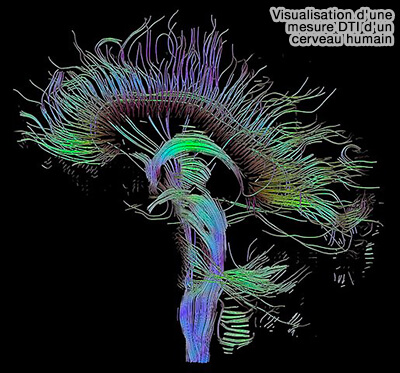

• Visualisation d'une mesure DTI d'un cerveau humain

Visualisation d'une mesure DTI d'un cerveau humain

(Figure : vetopsy.fr d'après Schultz)

IRM de diffusion (DTI ou dRMI)

L'IRM de diffusion (DTI ou diffusion tensor imaging) est une technique basée sur l'imagerie par résonance magnétique (IRM), qui permet de calculer en chaque point de l'image la distribution des directions de diffusion des molécules d'eau.

Cette technique est étudiée dans les méthodes de connectivité cérébrale est étudiée dans un chapitre spécial.